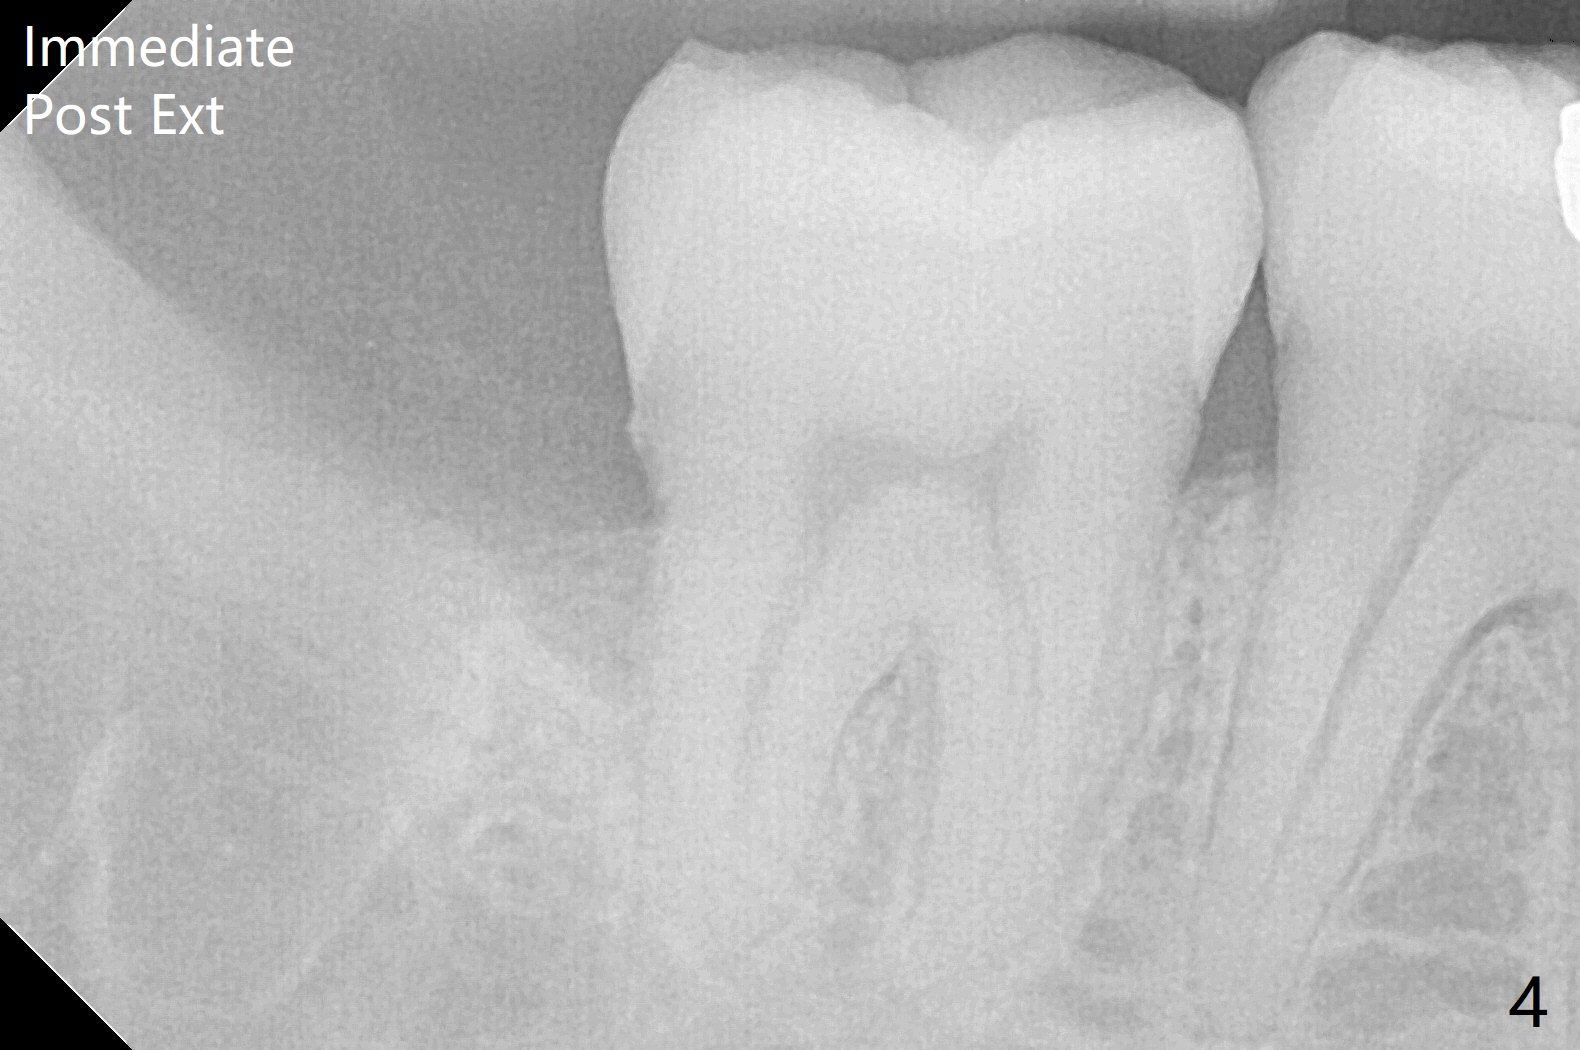

A 40-year-old man requests extraction of the teeth #17 and 32 (Fig.1). This case is designed to test that socket ossifies coronal when Collagen Plug is placed coronal. Release incision will be made both sides. Collagen plug will be placed at #32; none at #17. 4-0 PGA will be used to close the sockets. Photos will be taken immediate, 1 week, 1 month, and 3 months postop. PAs (sensor 1) will be taken immediate and 3 months postop. There is no wound dehiscence 1 week postop (Fig.6,7). The sockets reopen asymptomatic 3 weeks postop (Fig.8-11).